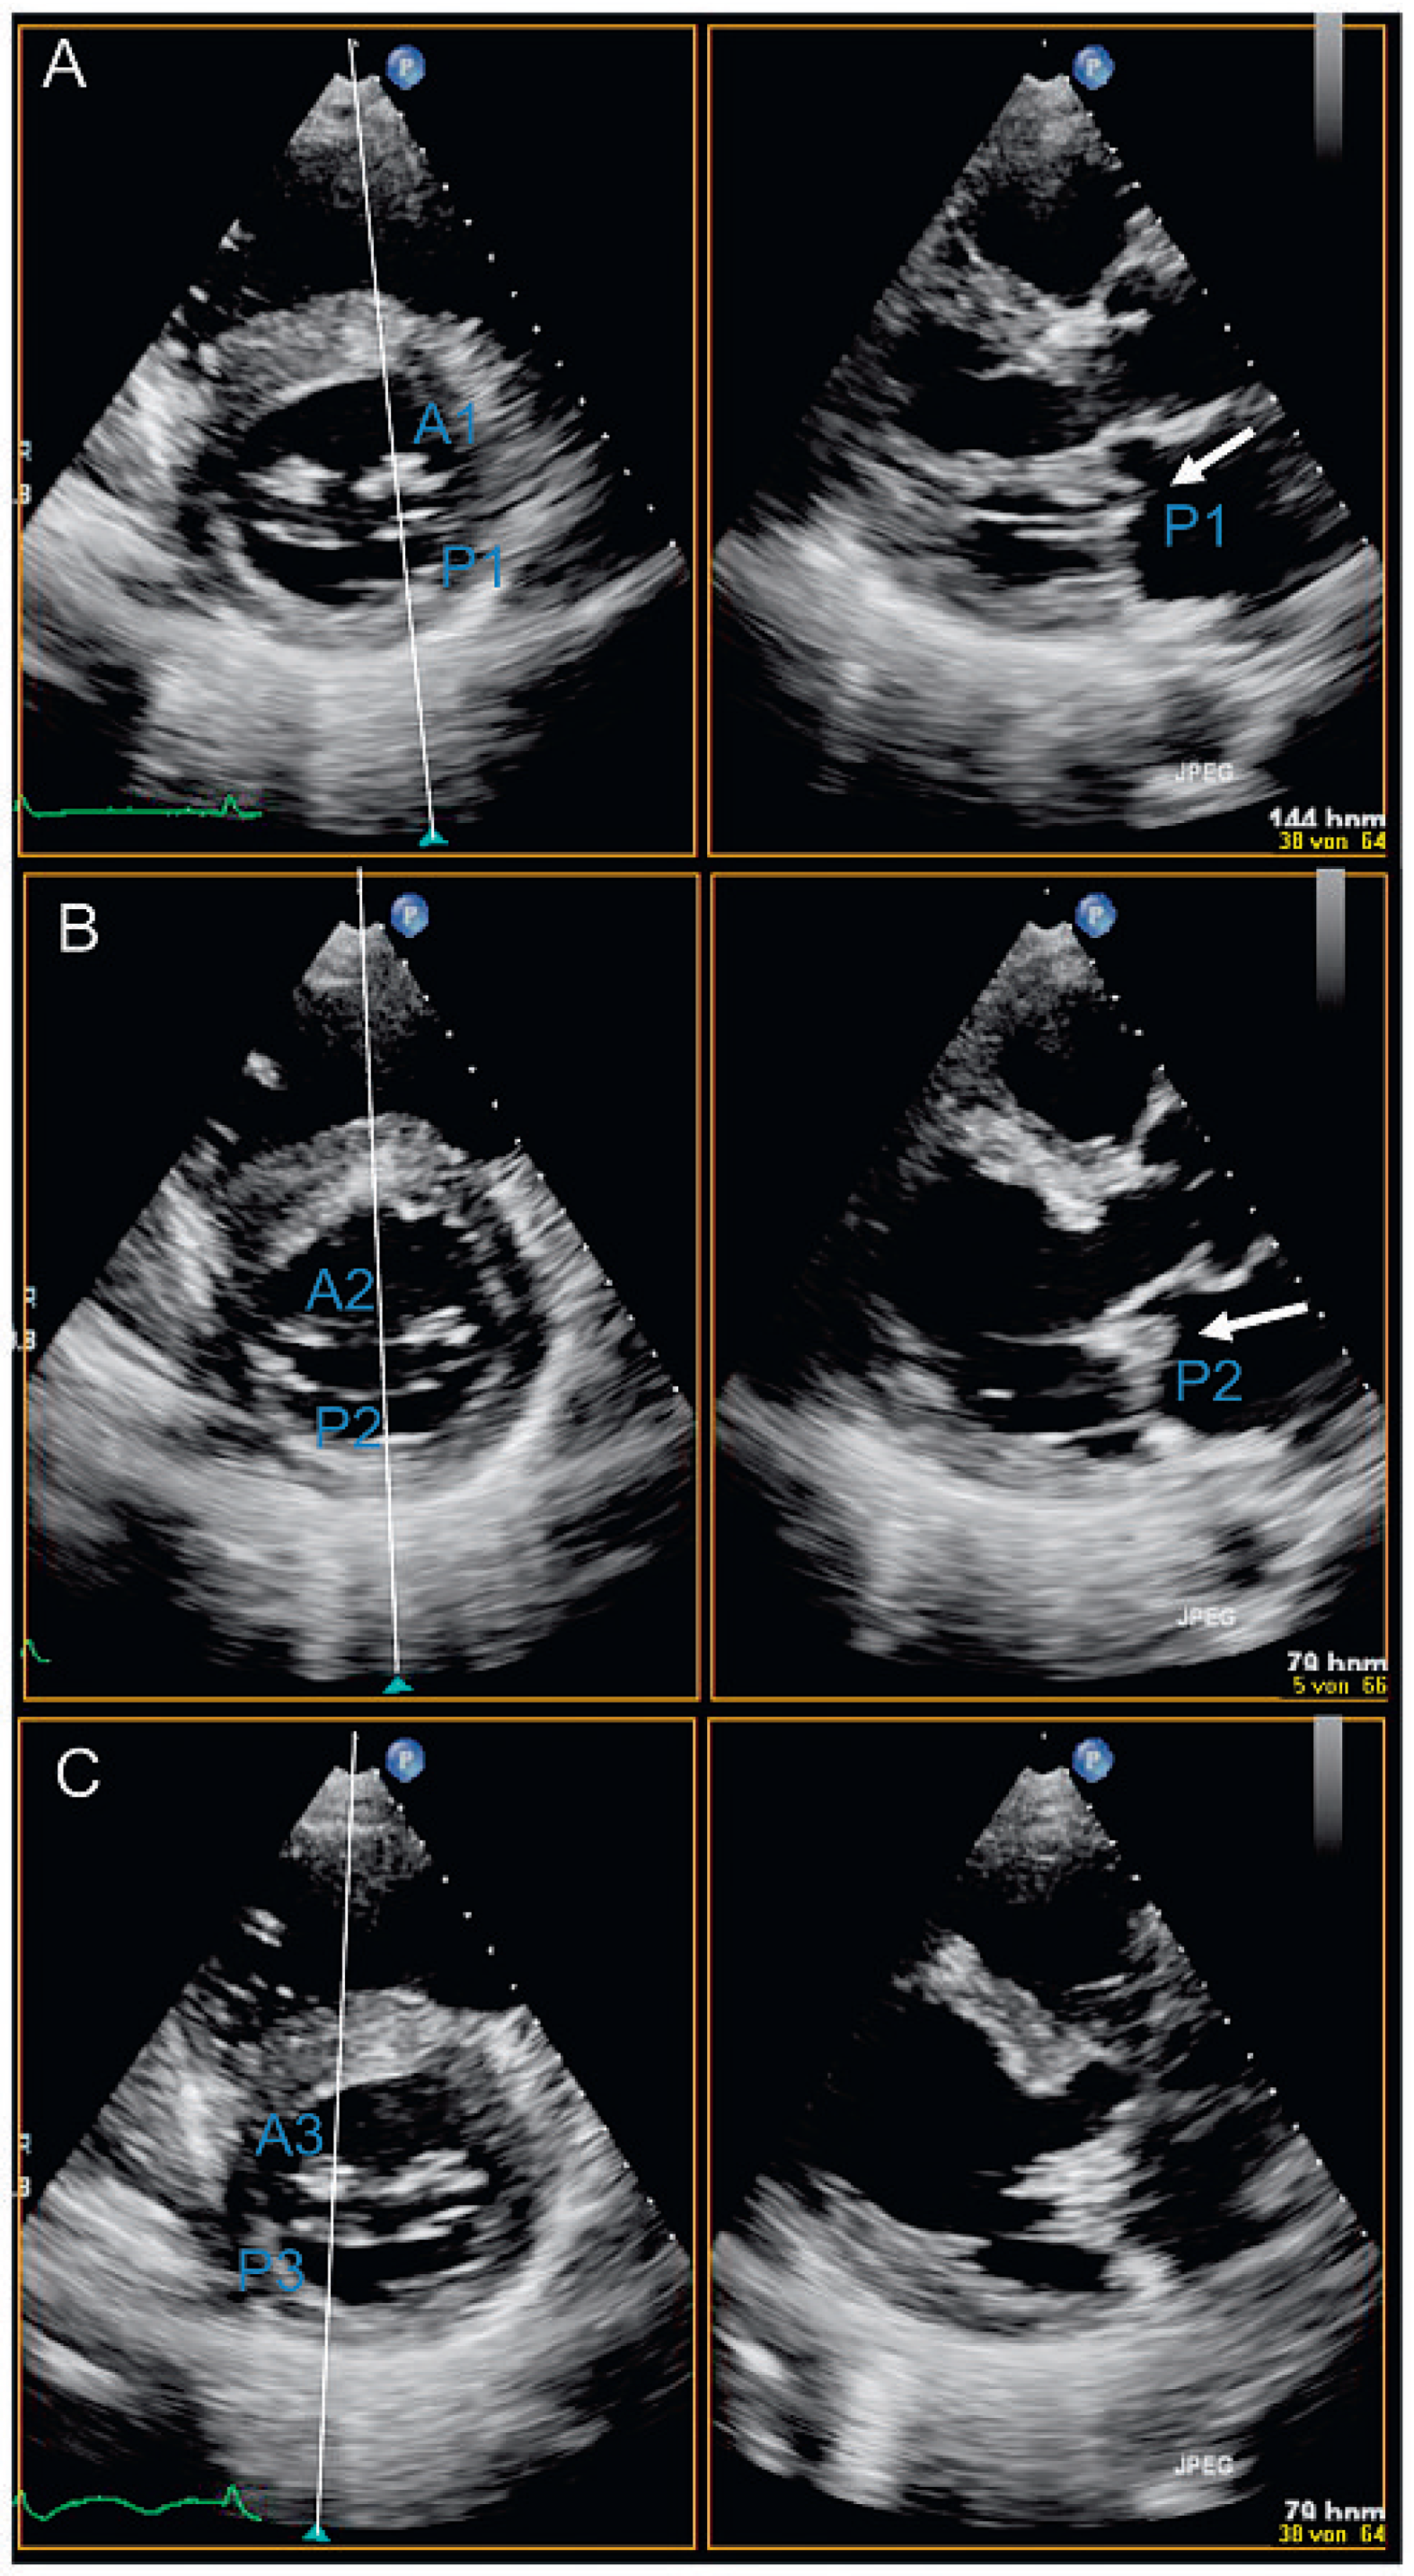

- «xPlane»: die Möglichkeit, gleichzeitig mehrere verschiedene Ebenen zu untersuchen, die in einem vom Untersucher wählbaren Winkel zu einander stehen (Abb. 1A). Zuschalten des Farb-Dopplers möglich (Abb. 1B).